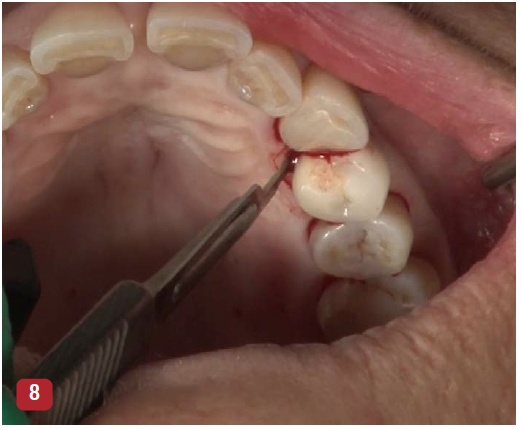

The incisions for VMIS around implants are similar to natural teeth but must be modified to accommodate the shape of the implant. A sulcular incision is made around the implant in the area of bone loss. The incision is extended to the mesial and distal as a split-thickness incision. This incision will extend to the line angle of adjacent teeth if present, or several millimeters into adjacent edentulous areas (Figure 8). A major difference in the use of VMIS on an implant is the removal of a section of connective tissue approximately 1-mm thick that is directly adjacent to the area of bone loss. Surgically, this is similar to the harvesting of a thin connective tissue graft (Figure 9). This step is performed to remove any microscopic particles of cement or titanium, which have been shown to penetrate the tissue and cause inflammation in cases of peri-implantitis.13